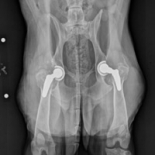

Background: A 9 year old female spayed German Shepherd Dog presents to the NCSU orthopedic service for hip dysplasia.

Overall Assessment: Bilateral hip dysplasia with severe DJD (Figure 1) and significant pain, as a consequence.